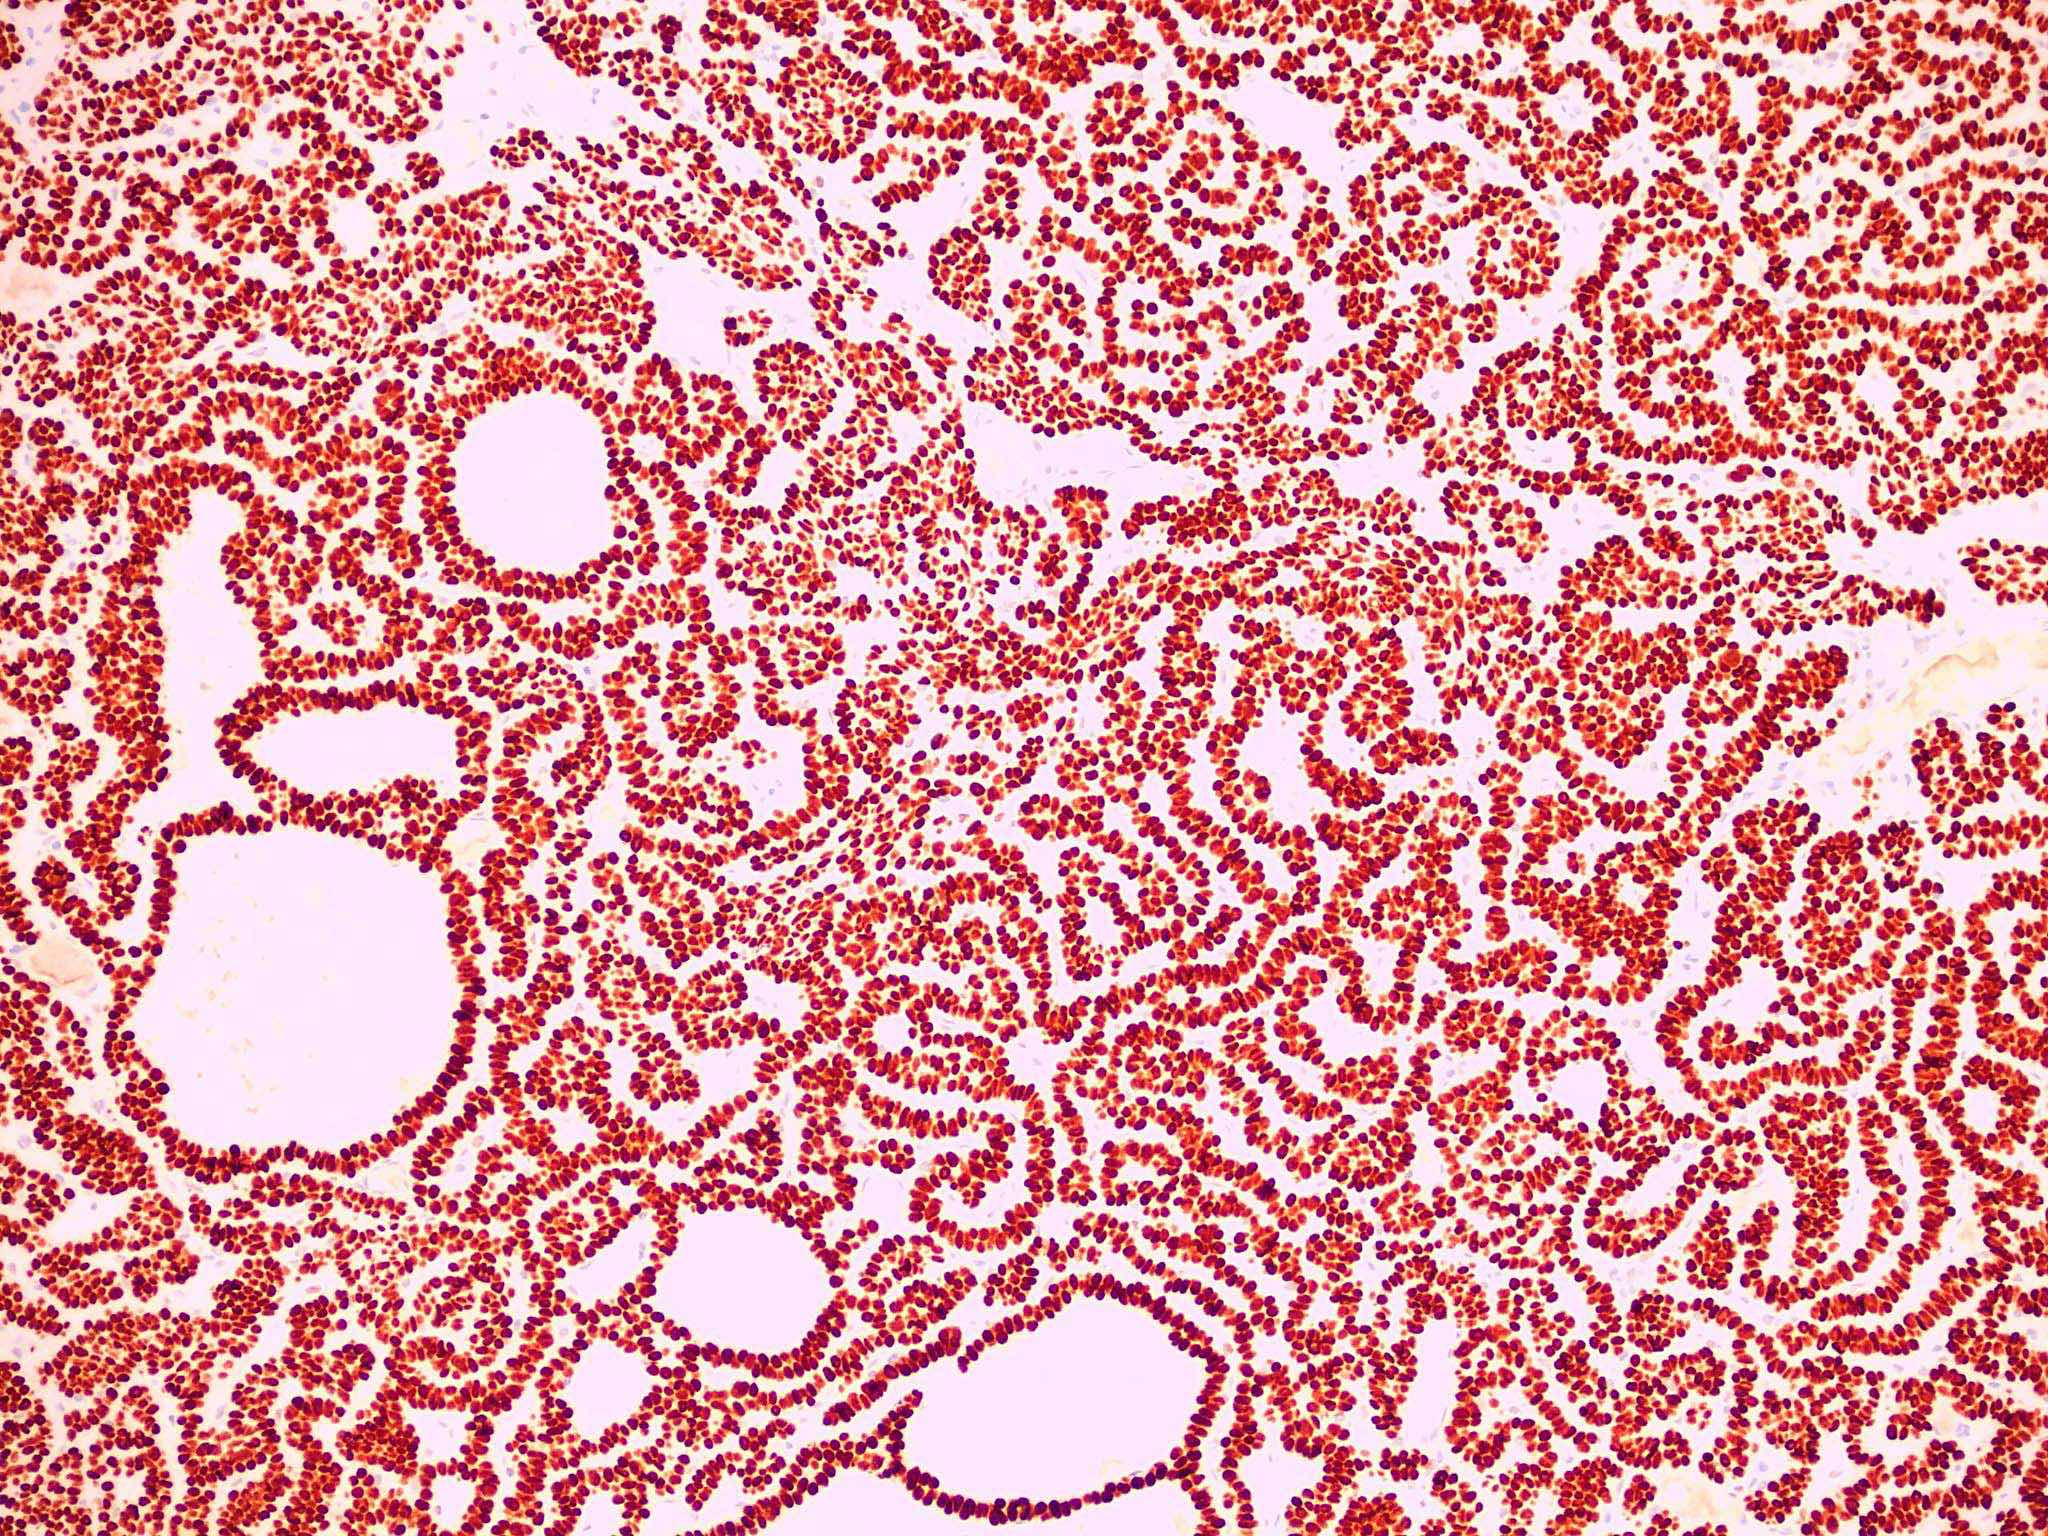

- Micronodular BCC

- Small basaloid nests

- Peripheral palisading less prominent

- Retraction artifact usually absent

- Can diffusely infiltrate the dermis and extend into the subcutis

Microscopic (histologic) images

Contributed by Antonina Kalmykova, M.D., Phillip H. McKee, M.D., Sate Hamza, M.D., Eduardo Calonje, M.D.,

Wayne Grayson, M.B.Ch.B., Ph.D., James Sampson, M.B.B.S., M.Sc. and Assia Bassarova, M.D., Ph.D.

Positive stains

- CK AE1 / AE3 (100%), BerEP4 (80 - 100%), p63 (100%), CAM 5.2 (20 - 95%), androgen receptor (33 - 66%), p53 (74.5 - 83%), 34 beta E12 (high molecular weight CK), BCL2 (diffuse pattern), CD10 (positive in tumor cells, negative in stroma) (Dermatopathology (Basel) 2015;2:15, Arch Pathol Lab Med 2017;141:1490, Rom J Morphol Embryol 2018;59:1115, Am J Pathol 1992;141:25)